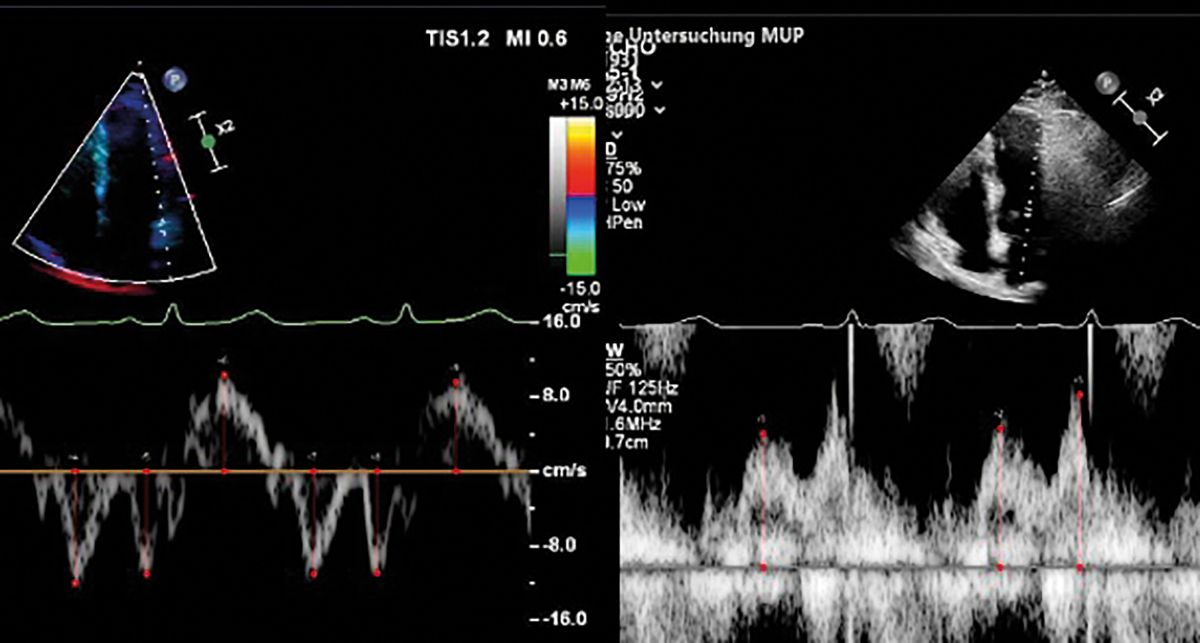

08.35 Uhr HFpEF im TTE: Was messen?

Wie interpretieren?

D. A. Morris

09.50 Uhr Stressechokardiographie: Indikationen

ausserhalb der Ischämiediagnostik

F.-P. Stephan

11.15 Uhr AI in der Echokardiographie

B. Kaufmann